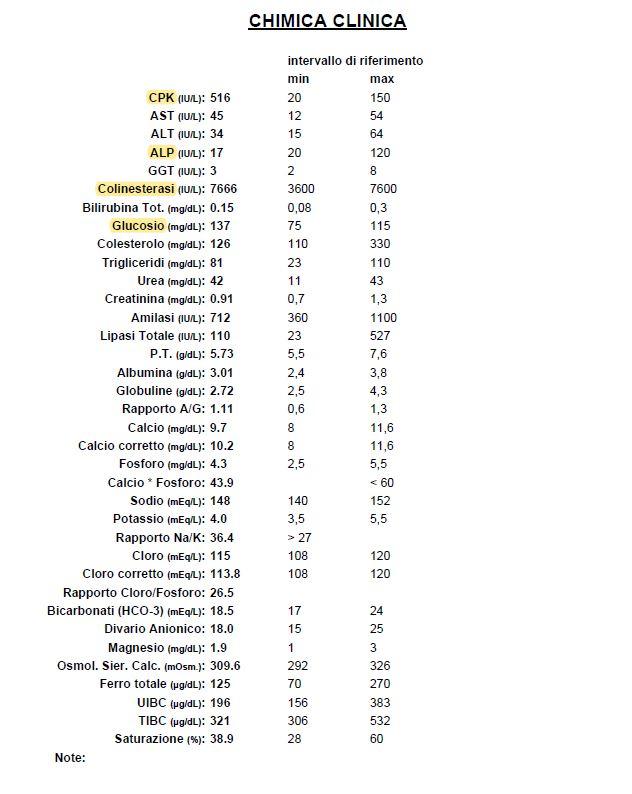

Vorrei chiedere, se possibile, il parere di un veterinario riguardo a degli esami del sangue fatti recentemente ad un cane di piccola taglia. Razza meticcia. Peso circa 9kg. Anni 9.

Chiedo qui perchè ho ricevuto gli esami per email, ma purtroppo è veramente difficile contattare i dottori telefonicamente, spero di passare presso l’istituto settimana prossima. Nel frattempo chiedo cortesemente consigli, dato che ci sono valori che forse non sono entro la norma.

Il cagnolino è stato portato in clinica perchè improvvisamente sembrava affaticato, aveva bisogno di sedersi durante la normale passeggiata. mentre solitamente è abituato a correre e giocare per tutto il tempo.

Specifico che ho evidenziato io i valori che , secondo me, risultano sbagliati. Ovviamente non ho nessuna competenza in materia.